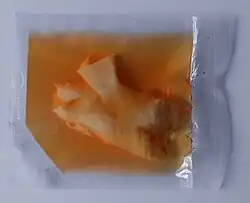

Сосудистый клапанный гомографт («гомографт» от лат. homograft, homo — человек, либо, в других интерпретациях, homogeneus – однородный, graft — трансплантат, протез) — имплантируемый протез, который полностью или частично состоит из неживых, специально обработанных тканей человека, включающих сердечные клапаны.

- криосохраненный клапанный гомографт (хранение в криоконсервирующей среде до 10 лет при температурах от −135 °C до −196 °C). В качестве хранилищ используются низкотемпературные морозильники, сосуды Дьюара и т. п.;

- свежеприготовленный клапанный гомографт (хранение в консервирующей среде до 3-х месяцев при температурах от 0 °C до +4 °C ).